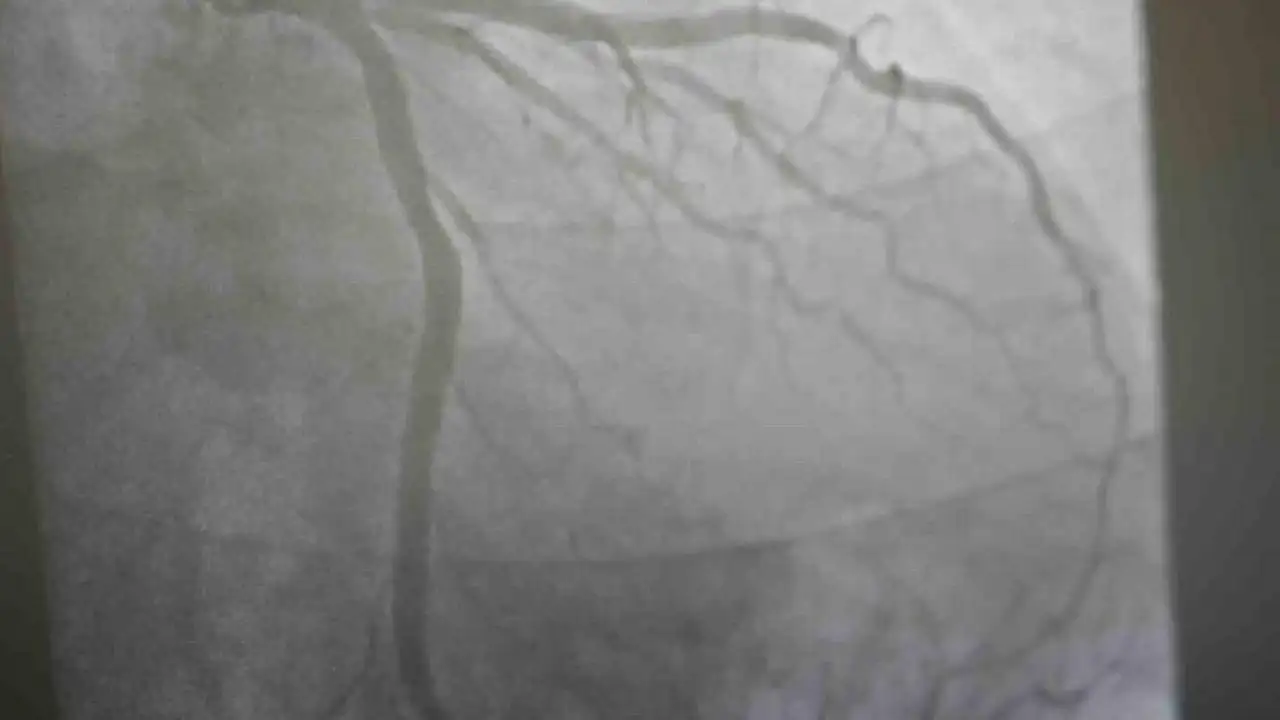

Aşıların kalp krizi riskine etkileri üzerinde açıklamalarda bulunan Medicana International Samsun Hastanesi Kardiyoloji Kliniğinden Prof. Dr. Uğur Arslan, "Covid-19 salgını sonrası kalp krizi olaylarında bir nebze artış hissettik. Ancak bu aslında beklenen bir şey. Direkt aşıları da suçlamamak gerekiyor. Çünkü aşılar hastalığı bir şekilde taklit ettikleri için insana daha hafif dokunsun diye bir miktarda olsa bu riski arttırabilirler. Covid'i bir grip gibi de düşünebilirsiniz. Artık yeni nesil grip biraz daha ağır geçiyor. Bu viral hastalıklar zaten genel olaraktan inflamatuar süreci başlattığı için kalp krizi gibi, koroner arter hastalığı inme gibi riskleri de arttırabilmektedir. Aşılar da bunlara dahildir. Az da olsa arttırmaktadır ama genel olarak bakıldığında kalp krizi için kişi Covid geçirseydi daha yüksek riske sahip olurdu diyebiliriz" diye konuştu.